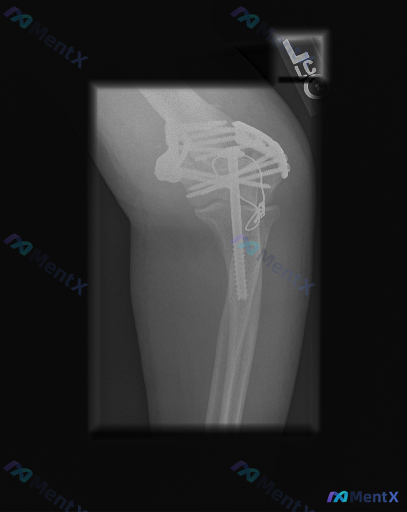

整理到一份肘部侧位X光的影像资料,先不说背景,大家看看这张片的异常,以及为什么会用这样的固定方式? 影像核心所见(先整理客观部分): - 体位:肘关节侧位,成人骨骺已闭合 - 内固定:桡骨头/颈区2枚平行螺钉;肱骨远端关节周围2枚植入物 - 骨性结构:桡骨头颈见陈旧骨折/术后愈合痕迹;无明显新鲜骨折...

网上整理到一份影像分析资料,先和大家分享一下: 原以为是肩部X光,实际是左侧肘关节侧位片,有“L”左侧标记。 主要影像表现: - 左侧肘关节肱骨远端、尺骨鹰嘴都是骨折内固定术后改变 - 肱骨远端看起来是双钢板固定,还有一枚长螺钉跨了髁间 - 尺骨鹰嘴有张力带样金属丝环绕 - 金属伪影很重,骨折线处骨...